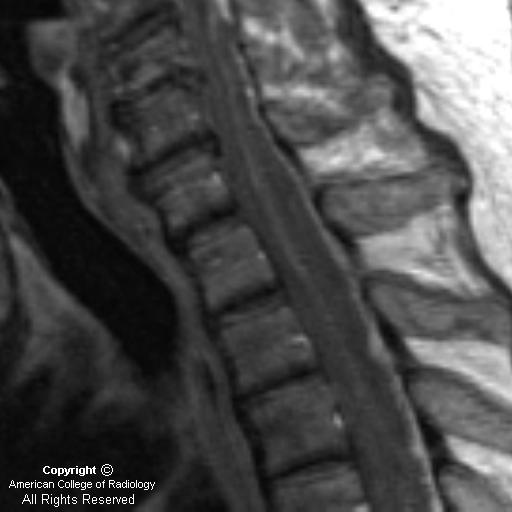

Sagittal T1 (Figure 1): There is an isointense posterior epidural mass that extends inferiorly from the C4-C5 disc space level and displaces the spinal cord anteriorly.

Sagittal T2 (Figure 2): The posterior epidural high-signal mass is more well-defined on this T2-weighted image.

MRI findings usually fall into 2 categories: 1) A soft tissue mass that is hypointense on T1-weighted images and hyperintense on T2-weighted images with diffuse homogeneous or slightly heterogeneous enhancement within the collection; 2) As the phlegmonous mass necroses, there may be a peripherally-enhancing fluid collection. Spinal epidural abscesses may be located anteriorly or posteriorly within the spinal canal. Anterior epidural abscesses are generally secondary to spread of adjacent infection from discitis or osteomyelitis. Posterior epidural abscesses may occur as a result of hematogenous spread of remote infections. Other causes of back pain that should be considered in the differential diagnosis include herniated disc, neoplasm, spinal hematoma, and transverse myelitis.